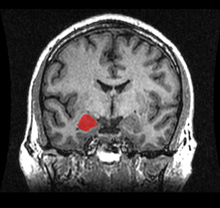

Location of the amygdalae in the human brain

Human brain in the coronal orientation. Amygdalae are shown in dark red.